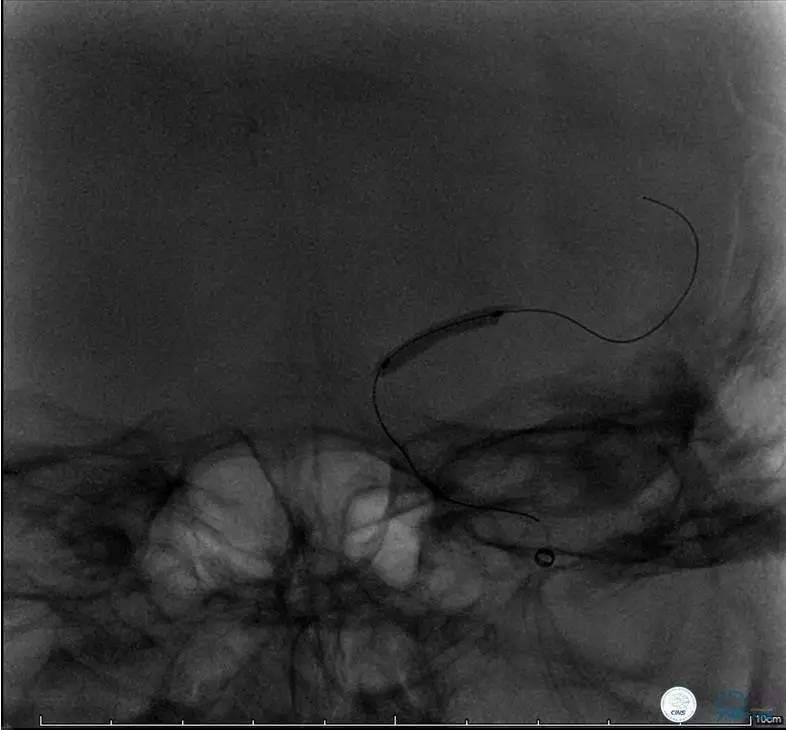

病例6

患者:49岁女性,脑梗死30天。

左侧颈内动脉末端闭塞,末端圆钝且有一定成角,开通难度较大,多次尝试导丝才成功穿过闭塞段。

开通效果很满意,术后症状明显恢复。